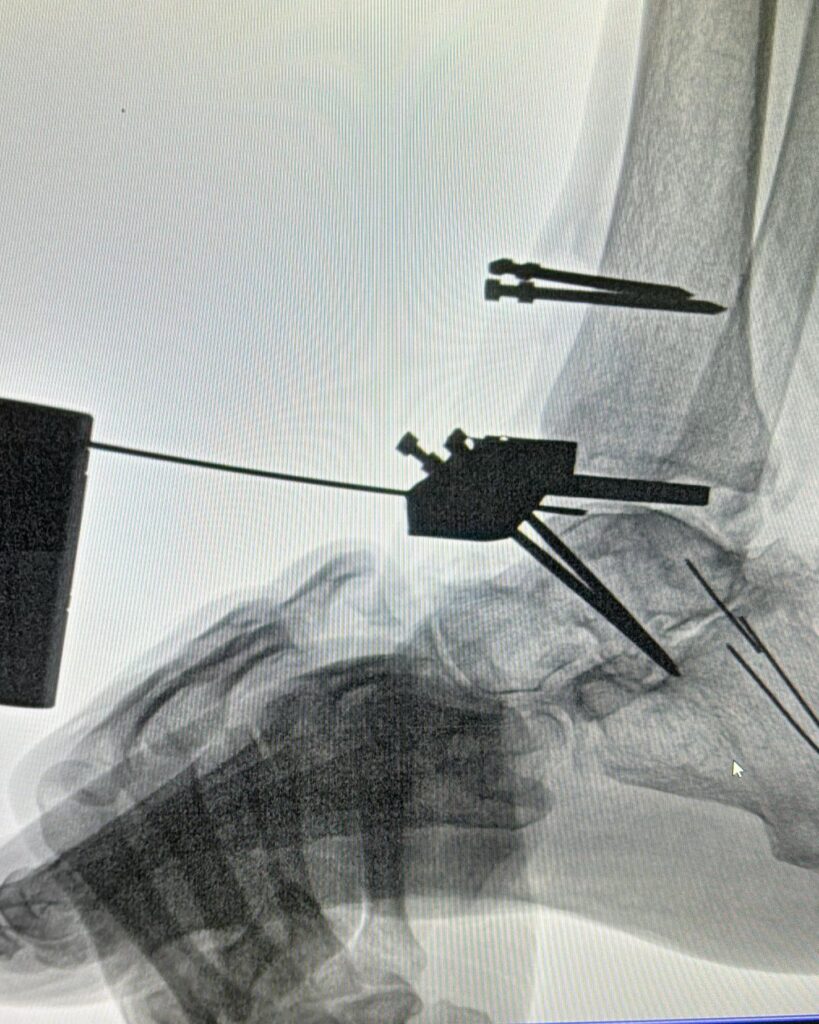

Este procedimiento quirúrgico consiste en sustituir la articulación dañada por una prótesis compuesta de metal y plástico, diseñada para restaurar la movilidad y aliviar el dolor.